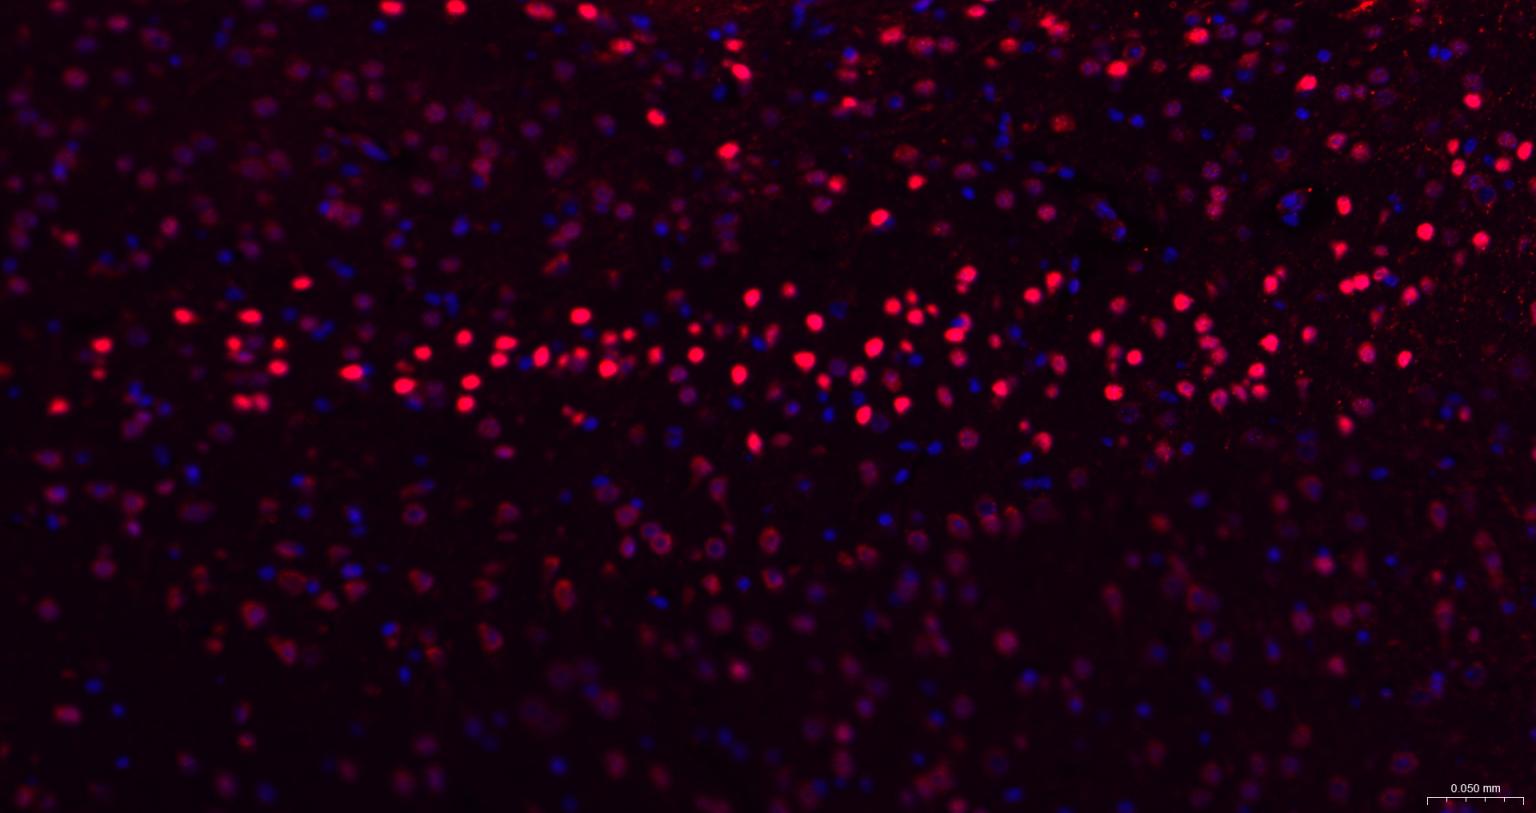

Paraformaldehyde-fixed, paraffin embedded Mouse Cerebrum; Antigen retrieval by boiling in sodium citrate buffer (pH6.0) for 15 min; The section was incubated with TBR1 Monoclonal Antibody, Unconjugated (bsm-60877R) at 1:200 overnight at 4°C. Followed by conjugated Goat Anti-Rabbit IgG antibody (Red, bs-0295G-BF594), DAPI (blue, C02-04002) was used to stain the cell nuclei.